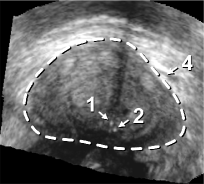

The framework was validated on 278 registrations of 295 US volumes from 17 patients. The 17 reference images were acquired shortly before the intervention, and the tracking images were acquired after a biopsy shot. The clinical protocol was approved by the ethical committee of the XXX hospital, Town, Country, and all patients consented to participate to the study. The images were acquired with a GE Voluson and a RIC5-9 endorectal US probe. The algorithms were executed on a 4-core 2.6Ghz processor. In order to provide a reference gold standard for the evaluation of registration accuracy, experts manually segmented 467 point fiducials that were clearly identifiable on multiple images (e.g. calcifications and cysts). The distances between fiducial pairs were measured after registration to estimate the local accuracy. Note that the unavoidable segmentation error increases the measured error in average; this approach hence underestimates accuracy. Accuracy was computed for all registrations that were qualified as valid by experts after visual inspection, which represent 97,8%percent\% of the registrations. The results for both rigid and elastic registration are given in Tab. 1, and a visual illustration of the registration performance is given in Fig. 2. Fig. 3 shows 3D biopsy maps created with our biopsy tracking system.

Figure 2: Fig. (a) shows a prostate volume with calcifications [1,2]. Fig. (b) shows a second volume after rigid registration; low probe pressure led to the low contrast zone [3]. Fig. (c) shows the 3D elastic registration with standard SSD; the whole prostate is dragged towards zone [3]. Fig. (d) shows the 3D intensity shift filtered, inverse consistent elastic registration; the strong intensity differences between both volumes are correctly handled, the calcifications make appearance at the correct position (best viewed in PDF with zoom).